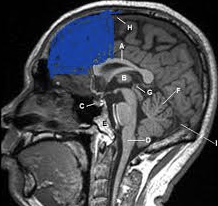

Lack of frontal lobe detected

View attachment 2294576

Negroids have literally have rounding projected foreheads where is this idea of lack of frontal lobe come from, are you talking about there actual brain. I believe they aren’t stupider just intellectually slightly inferior but they make up for it by being socially superior (swagmaxxed basically)